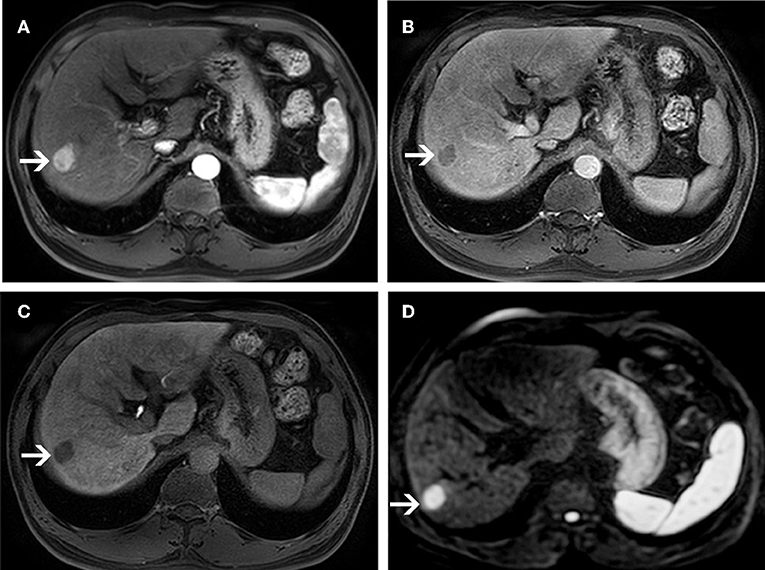

Figure 3. MR images of a 58-year-old man with a pathologically proven HCC (white arrows) and a history of hepatitis B virus infection. An arterial-phase image (A) shows an enhancing nodule in segment VI of the liver. An equilibrium phase MR image (B) shows a nodule demonstrating washout of contrast material, and showing capsular appearance. At the hepatobiliary phase (C), the lesion is hypointensity compared to the surrounding liver parenchyma. On diffusion-weighted image (D), the lesion is hyperintensity compared to the surrounding liver parenchyma.

Figure 4. MR images of a 66-year-old woman with a pathologically proven HCC (white arrows) and a history of hepatitis C virus infection. An arterial-phase image (A) shows a hypovascular nodule in segment I of the liver. An equilibrium phase MR image (B) shows a slightly hypointensity nodule compared to the surrounding liver parenchyma. A hepatobiliary phase image (C) shows a hypointensity lesion compared to the surrounding liver parenchyma. On diffusion-weighted image (D), the lesion is nearly isointensity compared to the surrounding liver parenchyma.